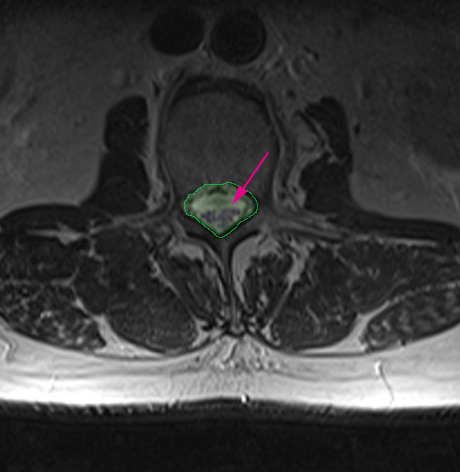

Φυσιολογικός ευρύς σπονδυλικός σωλήνας αριστερά (πράσινο) με άφθονο χώρο γύρω από τα νεύρα (βέλος). Στενός σπονδυλικός σωλήνας δεξιά με συμπίεση των νεύρων.